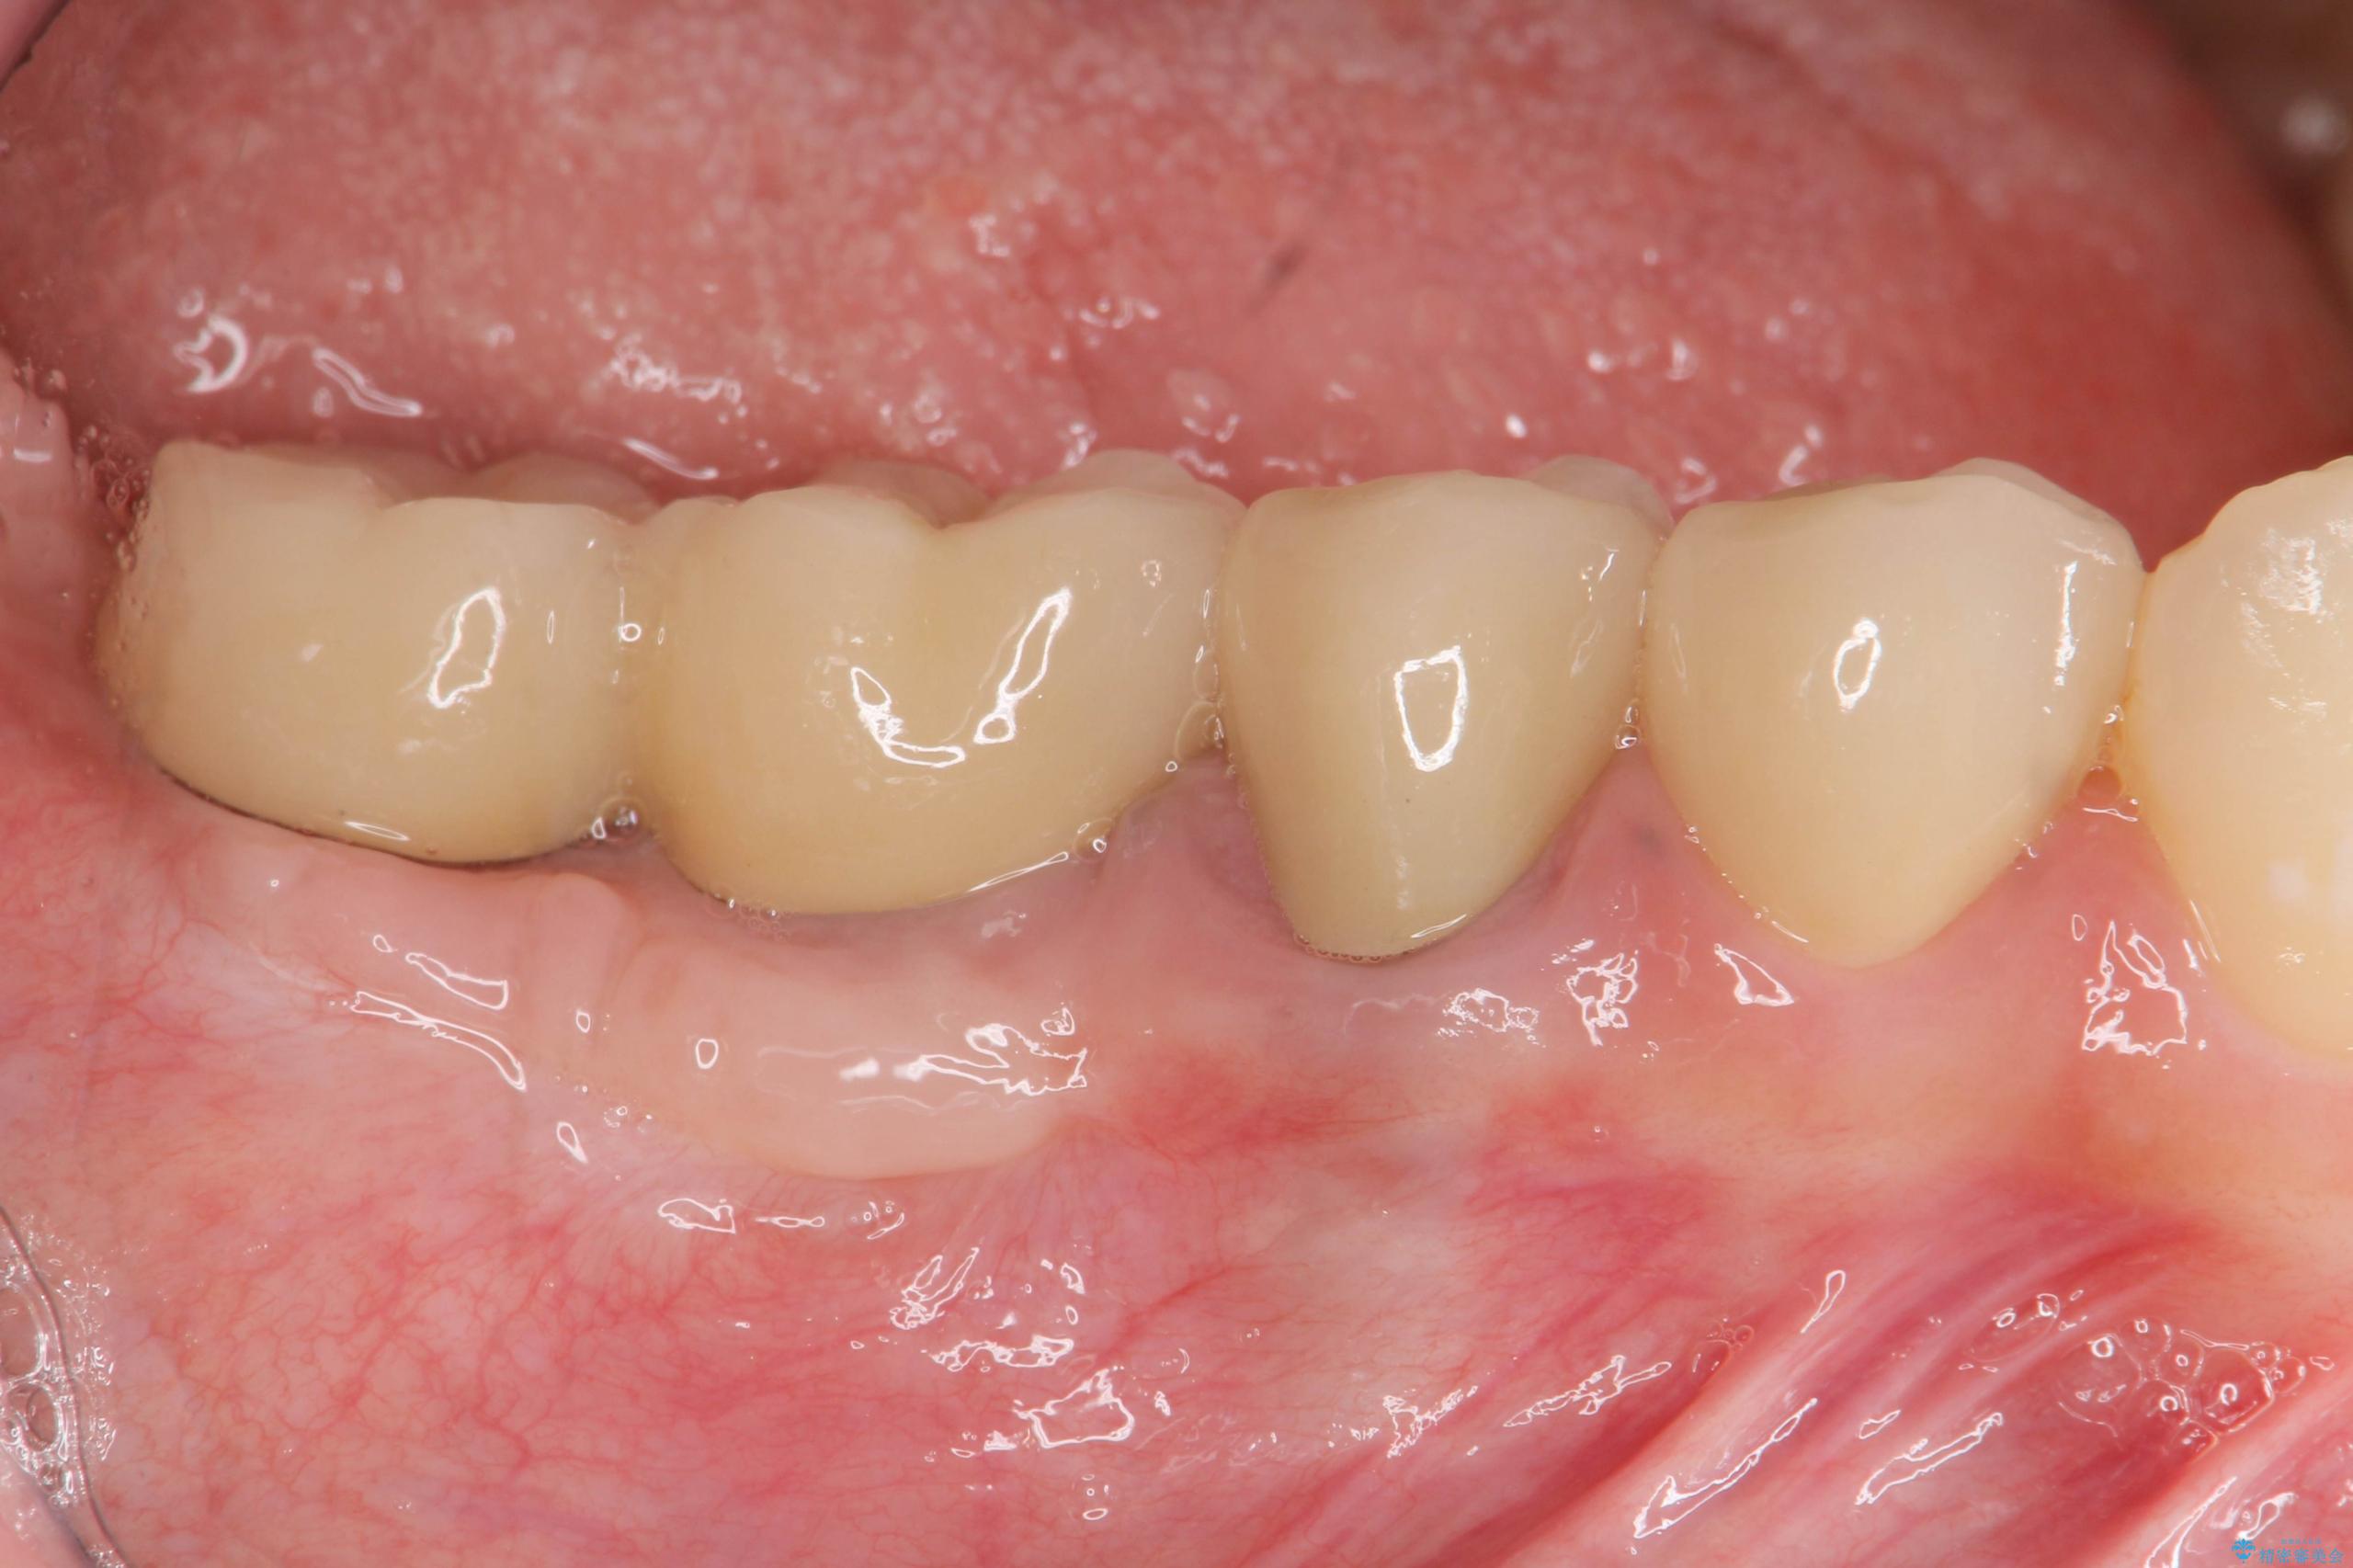

治療後

遊離歯肉移植術を伴うインプラント治療 治療後画像 遊離歯肉移植術を伴うインプラント治療 治療後画像 遊離歯肉移植術を伴うインプラント治療 治療後画像 遊離歯肉移植術を伴うインプラント治療 治療後画像